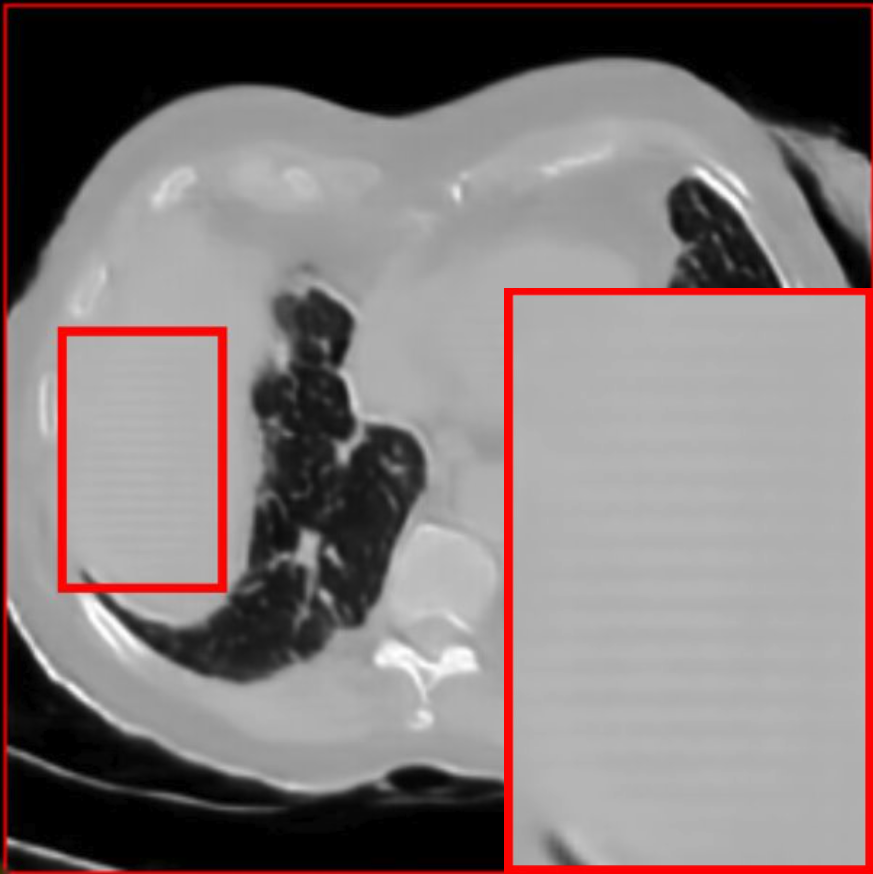

Figure 2: Qualitative comparison across axial (top row), sagittal (middle row), and coronal (bottom row) views. Columns correspond to different methods. MAISI-DDPM and MAISI-v2 in this figure are unconditional synthesis which do not use ControlNet or segmentation maps.

Qualitative Evaluation:

Figure 2 presents representative slices from the axial, sagittal, and coronal planes. GenerateCT (hamamci2024generatect) is a 2D model, so it lacks inter-slice consistency, leading to poor image quality in the sagittal and coronal views. MedSyn (xu2024medsyn) produces noticeably blurry results with mosaic-like artifacts, such as region inside the red box. HA-GAN (sun2022hierarchical) generates visually sharp images but with mosaic-like artifacts, such as region inside the red box. Also, its voxel spacing is not available, which limits its applicability in real-world medical imaging tasks. Moreover, all three methods are restricted to synthesizing small anatomical regions. In contrast, both MAISI and MAISI-v2 are capable of generating high-quality 3D volumes that span larger body regions while preserving fine anatomical details and realistic structure.